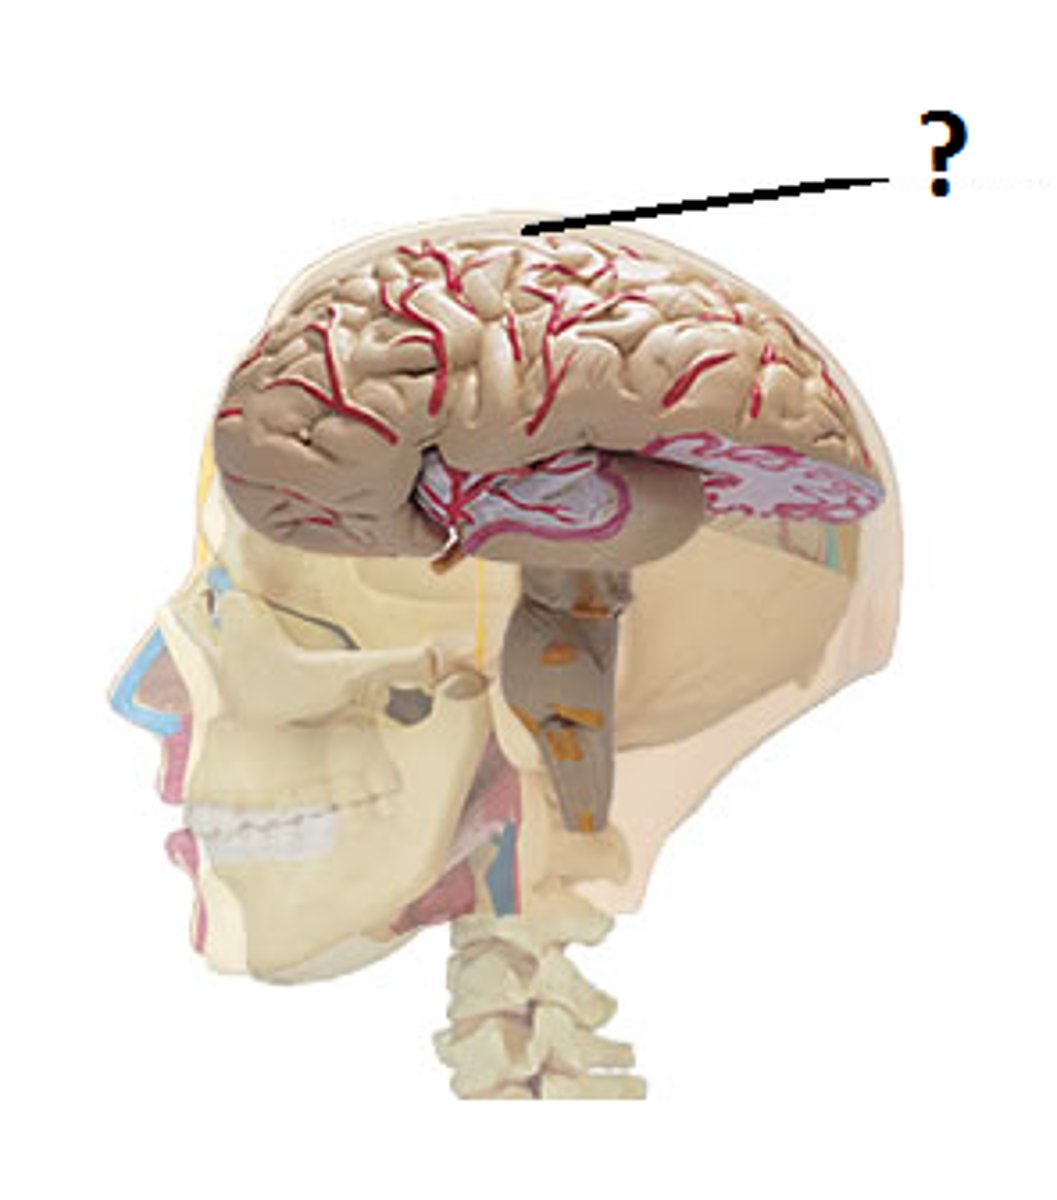

Cerebral cortex

outermost part of forebrain; controls voluntary muscular movements as well as sensation, movement, memory, emotions, and executive function